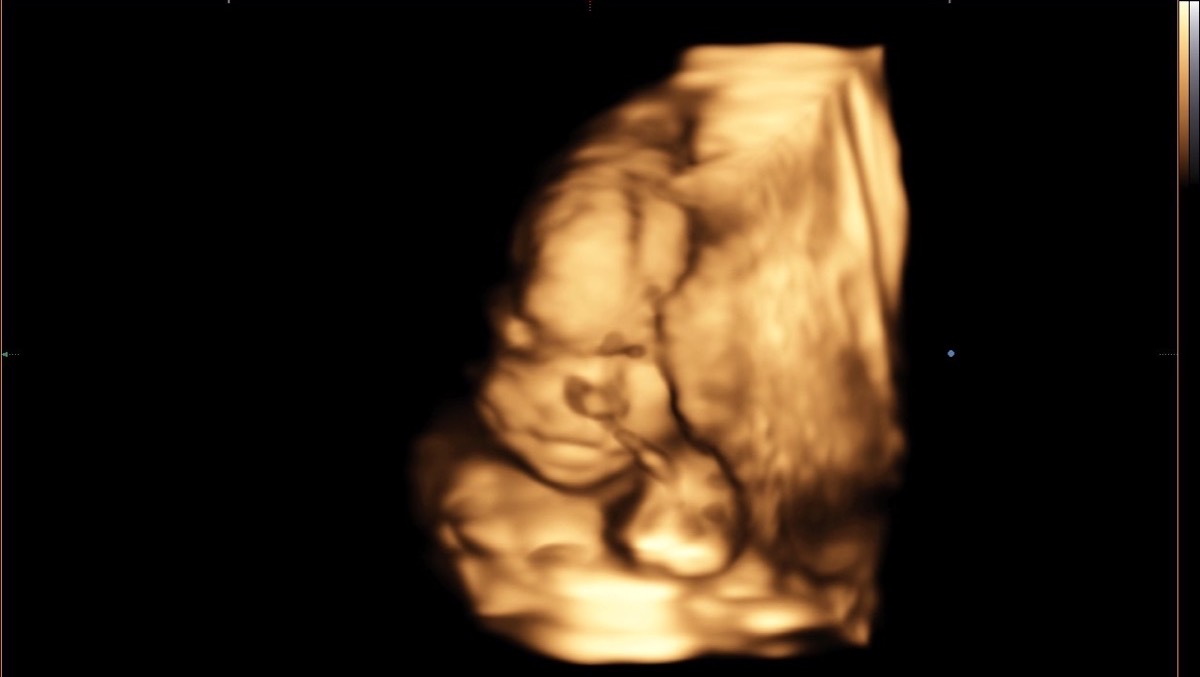

At the end of August of this year, when I woke up in the morning, I felt that something in my life had changed. But I couldn't understand what. After taking a pregnancy test, the results it was confirmed I'm pregnant. At first I was scared, but our inner feeling of happiness and joy overwhelmed us so much that we did not believe this was happening to us. I immediately began to take care of my child. I visited doctors regularly, took all the tests, ate right, walked by the sea and in parks, talked every day with the baby. I can’t express the emotions I felt when for the first time in my life I heard my child’s heart on an ULTRASOUND. The emotions i felt After the doctor proclaimed “Congratulations, you have a healthy girl.” Many years ago we came up with names for our children - Vasilisa; and already began to talk with her more and more, talked about what color her room would be and how we would all go to my grandmother's in the summer, how we would definitely get a dog ...

On the ultrasound, the specialist said that he couldn’t understand why he couldn’t see the right side of the diaphragm and saw some strange shadow in the place of the right lung. I didn’t understand what she was talking about at all, and after that I was sent to a specialist at the genetic center. The next morning we went to this center, during the ultrasound we cried and could not stop.

The doctor announced that our girl had a Right-sided diaphragmatic hernia. This is a very rare physical pathology, when a defect occurs in the diaphragm and the abdominal organs rise up through this defect and block the lungs, displacing the Heart. Only 15% of all registered cases will fall to the share of the right-sided one. In our country there is not a single specialist or technical ability to help such children, and that she will die within a few minutes after birth. Without an ECMO device, which is not available in Ukraine, only intrauterine surgery and surgery after birth can help her, but this is not done in our country.

After all, we were given a referral for Artificial Termination of Pregnancy. I could not take this step, because already at that moment I felt every day how my girl was moving and beating inside me. I knew that my child was healthy and had no chromosomal and genetic pathologies. After we decided to conduct all existing in-depth studies, our girl was checked by many specialists. They did an ultrasound, an MRI of the fetus, an ultrasound of the baby’s heart, they took an amniocentesis, all this in order to exclude any pathologies, a consultation was held. In conclusion, it was indicated that the child Congenital right-sided diaphragmatic hernia, all indicators of the lungs were calculated, that in other respects the girl is healthy and that she can be saved only with the help of intrauterine surgery. Through punctures in the abdomen at the 28th week of pregnancy, a balloon is inserted into the trachea, thanks to which the lungs grow and push out extra organs from the chest, which after birth will allow the baby’s lungs to work, and the defect in the diaphragm is sutured with its own tissues, after the child’s condition stabilizes, we contacted the Sant Joan de Deu hospital, namely Eduard Gratakos, who is a leading specialist in fetal surgery. He was one of the first to carry out such operations in the world, he said that he could and knew how to help us, that he had already performed similar operations and the children survived. He would try to do everything in his power. The cost of a fetal operation and assistance to a child after birth is 170,000 euros, this amount is unbearable for our family. We are forced to seek help, now I am 23.5 weeks pregnant. Thanks to everything that has happened to us lately, we know and believe that our girl can be helped, and we will never forgive ourselves for not trying to do it. I could not terminate the pregnancy according to indications in my country, knowing that my child is healthy, because every day I feel her inside, I feel how she actively moves when I eat something sweet, when I play the piano, when I sing, she especially likes it ... we love our girl very much . We are very scared, but we hope and believe that everything will work out for us. Our strong girl will also cope with all the trials that fell on her ...